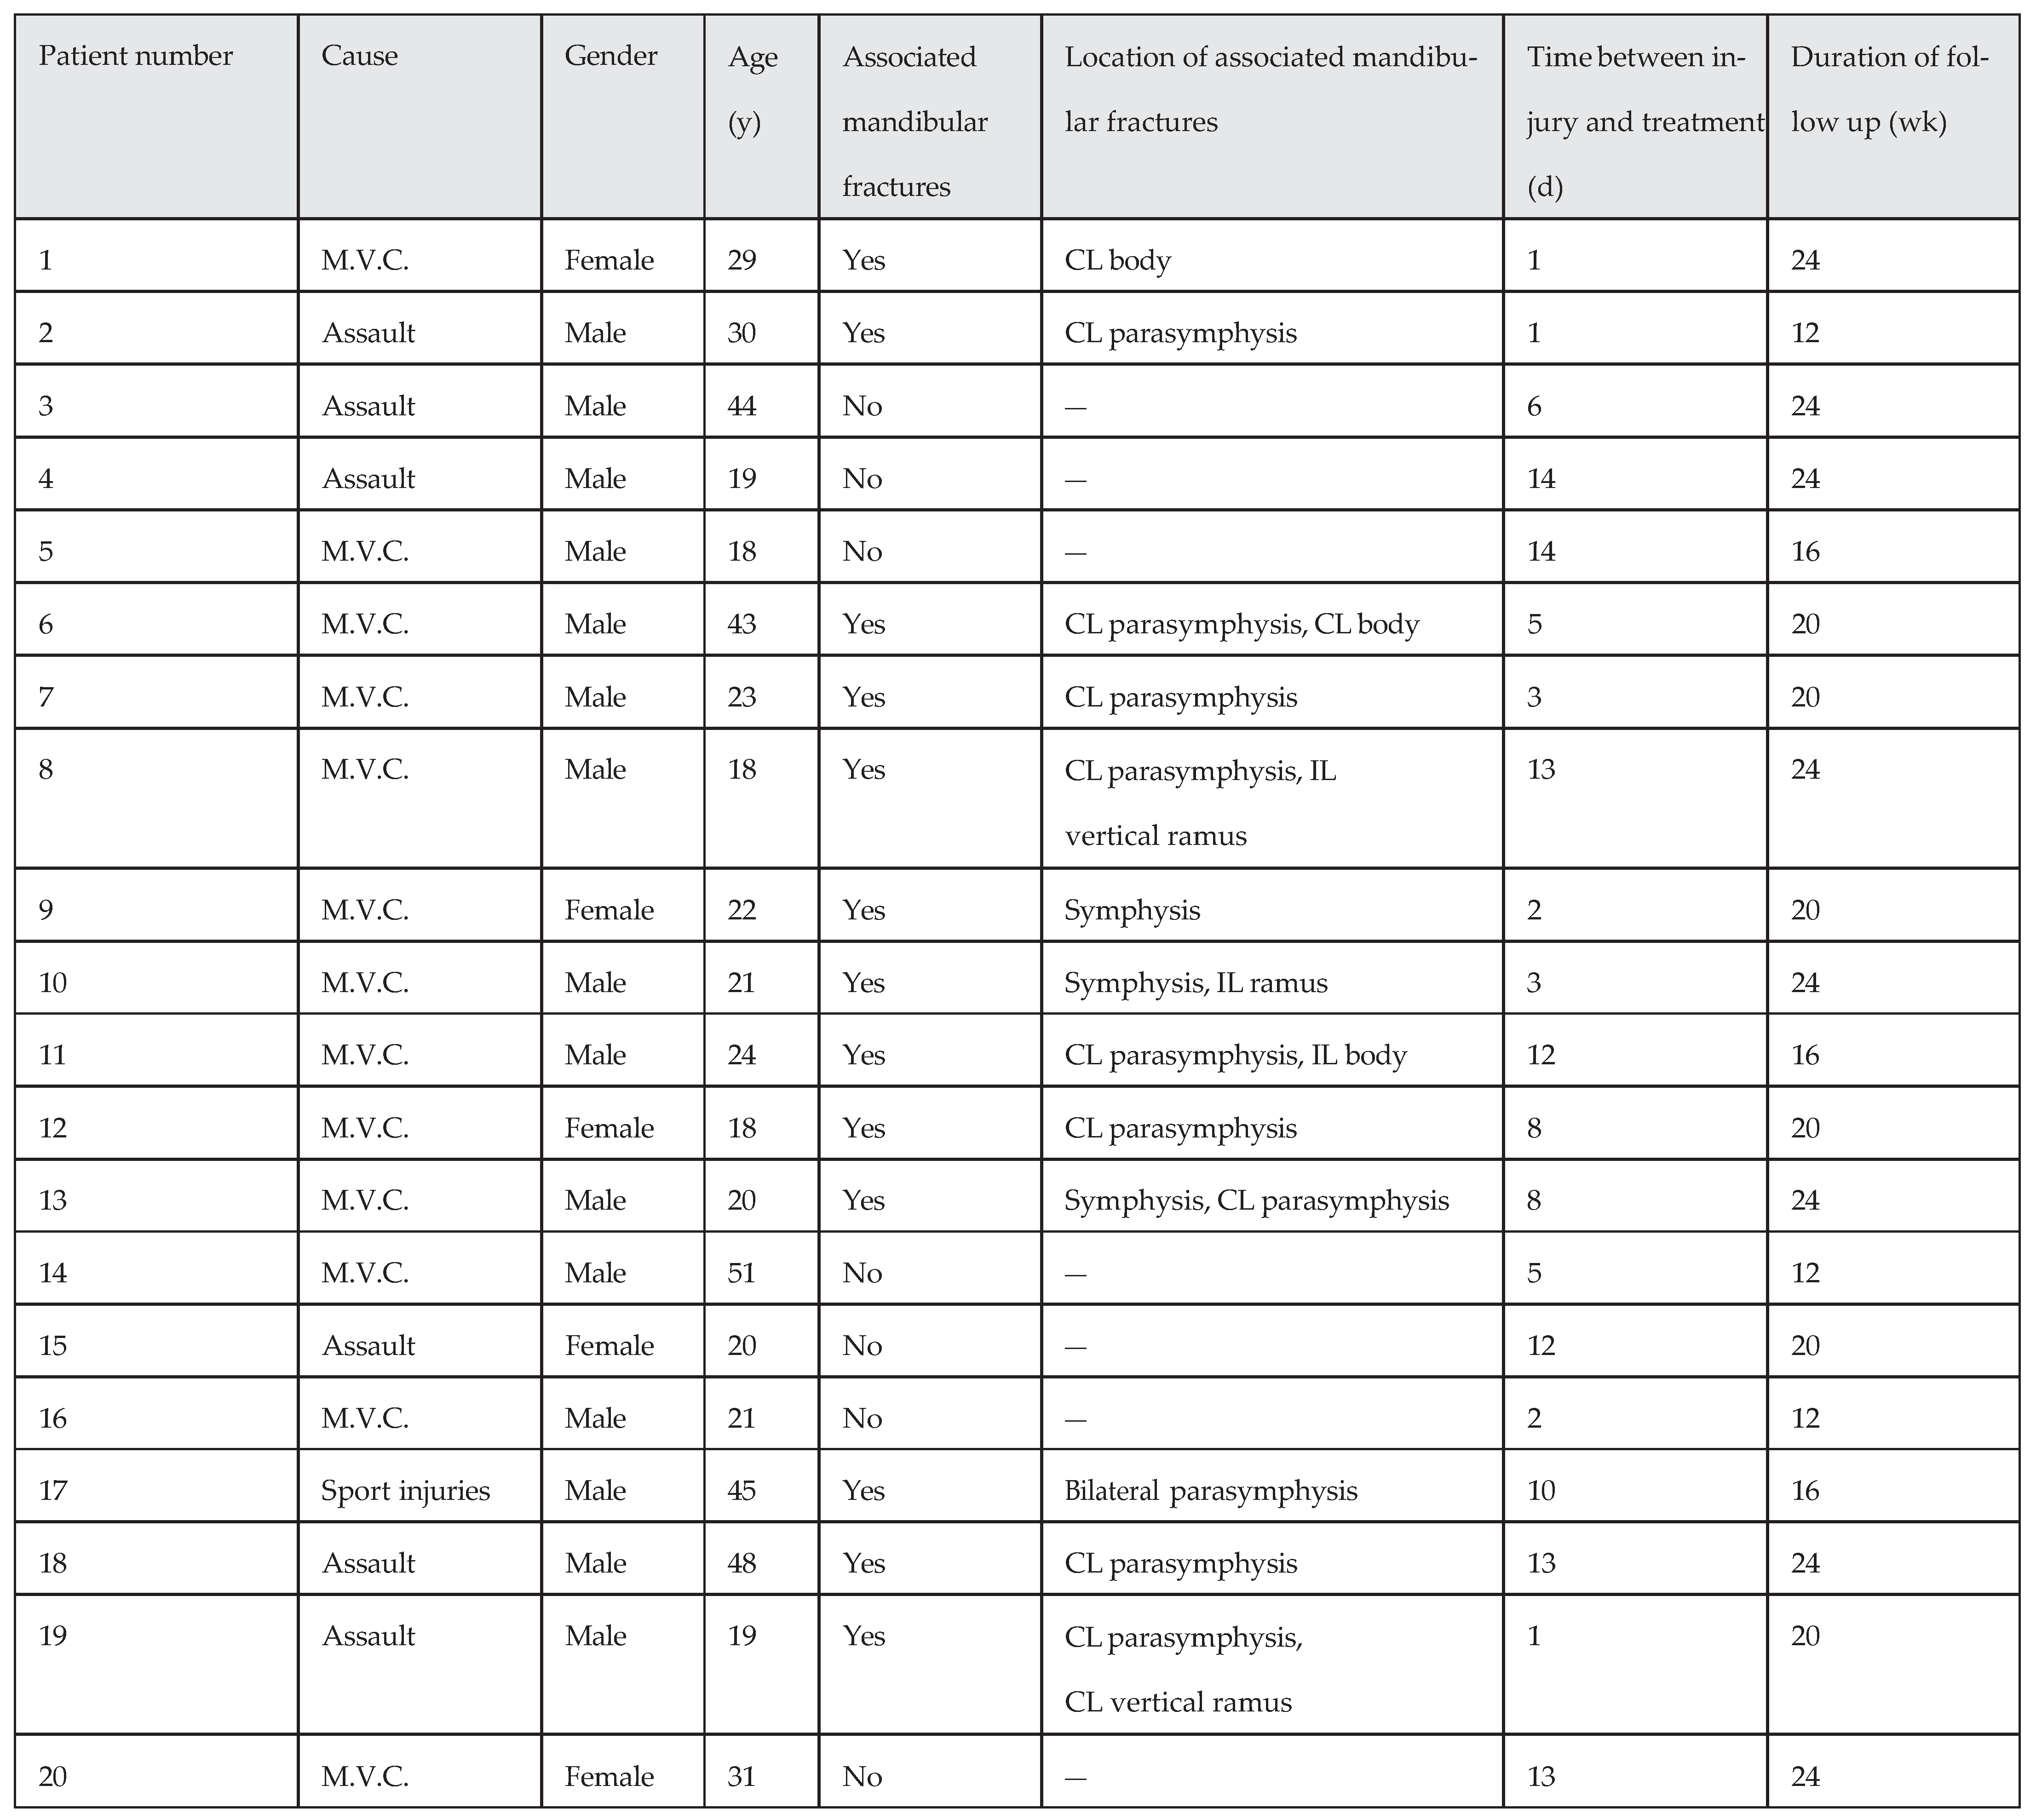

Second Treatment Group (with Rigid IMF) Results

Five patients were women and 15 patients were male, with ages ranging from 18 to 51 years (mean ¼ 28.2 11.41;

Table 2). Seven patients (35%) had an isolated mandibular angle fracture and 13 patients (65%) had associated fractures. Six patients (30%) had a tooth in the mandibular angle fracture line. The mean follow-up period in this group was 19.90 4.42 weeks, and the mean time between injury and surgical operation was 7.30 4.94 days. In the follow-up period, two patients (10%) were noted with one postoperative complication each. One patient showed infection identified 10 weeks after the operation. The patient’s symptoms were swelling and tenderness at the surgery region. The miniplate was removed subsequently under local anesthesia; the mandible was stable at the time of the plate removal and the wound healed without further event. This patient had a tooth at the angle fracture line, which was removed at operation time.

One patient had malocclusion postoperatively, which was treated by elastic therapy successfully after IMF removal. This patient had no teeth at the angle fracture line but had other fractures in the mandible (contralateral body fracture).

Results were analyzed by means of nonparametric statistical tests. The incidence of complications was analyzed between the two treatment groups by the Mann-Whitney test (p ¼ 0.79 for the first treatment group and p ¼ 0.72 for the second treatment group, not significant).

In the two groups, the incidence of complications was analyzed with the presence of the third molar and other mandibular fractures separately. This analysis, performed by Wilcoxon test gave p values of 0.56 and 0.83 (for the first group), and 0.2 and 0.10 (for the second group), respectively (not significant).